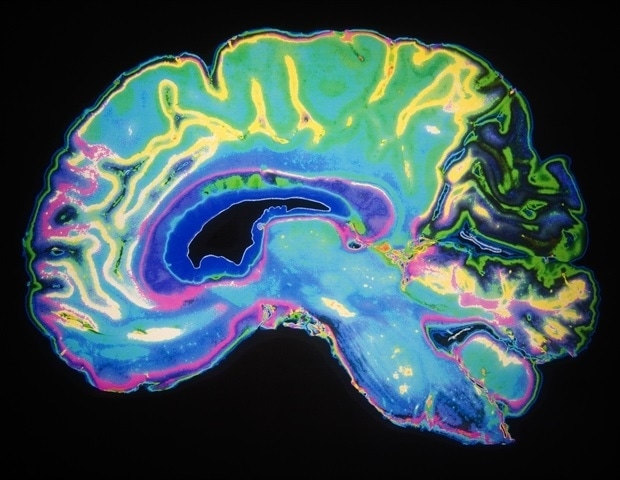

Ο χάρτης αποκαλύπτει την ανάπτυξη του αγγειακού δικτύου στον εγκέφαλο του ποντικού

Μια σημαντική πρόοδος στην αναπτυξιακή νευροεπιστήμη σημειώθηκε με τη δημιουργία του πρώτου λεπτομερούς χάρτη που καταγράφει πώς αναπτύσσεται το αγγειακό δίκτυο στον εγκέφαλο του ποντικού μετά τη γέννηση. Η μελέτη αυτή δημοσιεύθηκε στο περιοδικό Cell.

Αυτό που προκύπτει από τη μελέτη είναι ότι η ανάπτυξη των αιμοφόρων αγγείων στον εγκέφαλο δεν ακολουθεί απλώς τη διαδικασία ανάπτυξης των νευρώνων. Αντιθέτως, η ανάπτυξή τους διαμορφώνεται από μια δυναμική, πολυφασική διαδικασία που διαφέρει ανάλογα με τις περιοχές του εγκεφάλου και σχετίζεται άμεσα με την ωρίμανση των νευρωνικών κυκλωμάτων, αναδεικνύοντας έτσι έναν ενεργό ρόλο των αιμοφόρων αγγείων στην κατασκευή του εγκεφάλου μετά τη γέννηση.

Ένας από τους κύριους στόχους της έρευνας είναι η αναγνώριση τριών διαδοχικών φάσεων στην ανάπτυξη των αιμοφόρων αγγείων μετά τη γέννηση. Η πρώτη φάση περιλαμβάνει την συντονισμένη ανάπτυξη των αγγείων και του εγκεφάλου, η οποία διασφαλίζει επαρκή παροχή αίματος τις πρώτες μέρες της ζωής. Η δεύτερη φάση χαρακτηρίζεται από ταχύτερη ανάπτυξη των αγγείων σε σχέση με τον εγκέφαλο, επισημαίνοντας τη σημαντική επιβάρυνση του αγγειακού δικτύου. Αυτή τη στιγμή μπορεί να αντιστοιχεί σε πρώιμη παιδική ηλικία και στην περίοδο της σχολικής ηλικίας, μία εποχή που η ανάπτυξη των νευρωνικών κυκλωμάτων είναι εντατική.

Τέλος, η τρίτη φάση αναφέρεται στην σταθεροποίηση και την τελειοποίηση του αγγειακού δικτύου, που ενδέχεται να συνδέεται με την εφηβεία, όταν η αγγειακή αρχιτεκτονική αποκτά μια πιο ώριμη δομή μπορεί να προσαρμοστεί σε νέες ανάγκες. Η μελέτη αυτή μας προσφέρει πολύτιμες πληροφορίες για τις φάσεις ανάπτυξης των αγγείων, οι οποίες δεν είναι ομοιόμορφες σε όλο τον εγκέφαλο, αναδεικνύοντας τη σημασία των ειδικών σημάτων σε διάφορες περιοχές του εγκεφάλου.